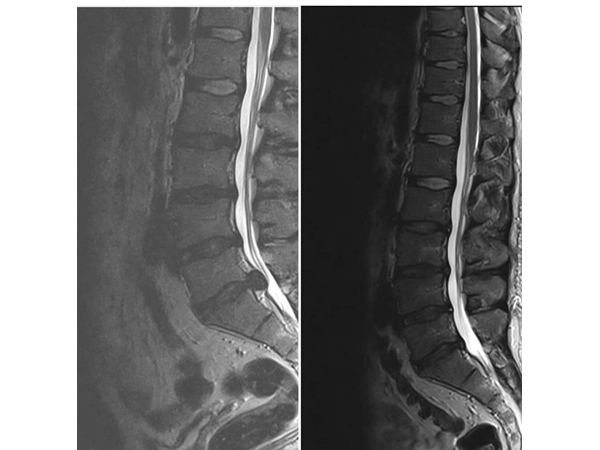

Najčešći problem bolnih ledja je diskus hernija koja se obično javlja između 30 i 50 godine života.

Simptomi zavise od nivoa u kom se javio problem. Najčešće se javlja u nivou L5/S1, tada bol ide duž čitave noge sve do stopala, obično je prisutan i bol u listu uz jak spazam mišića,a može doći i do pada stopala, kao i oštećenja sfinktera ( učestalo mokrenje, nemogućnost mokrenja, erektilna disfunkcija).

Dekompresiona terapija kičme je jedini neoperativni tretman, kompjuterski kontrolisan i dijagnostički povezan, koji postiže odlične rezultate kod teških slučajeva diskus hernije, degenerativnih promena, artritisa, stenoze spinalnog kanala i pritiska na nervne korenove.

Dekompresiona terapija deluje tako da putem cikličnih faza distrakcije i relaksacije i pravilnom pozicioniranjem diska dovodi do povećanja međupršljenskog prostora za nekoliko milimetara (1-2), oslobađa živce - između njih, smanjuje bol, trnjenje, glavobolje, vrtoglavice, kao i slabosti u šakama i stopalima.

Ovaj tretman stvara negativan pritisak i efekat vakuma u samom diskusu koji se nalazi izmedju dva pršljena i na taj način povlači herniju unutar diska.

Vakum povećava cirkulaciju oko diska i tako leči upalni proces.

Dekompresijski tretman vrši istezanje receptora u mišićima i ligamentima oko kičmenog stuba, smanjuje pritisak na medjupršljenske zglobove povećavajući pokretljivost kičme.

Zatim odvaja, odnosno vrši separaciju pršljenova i povećava prostor izmedju njih, proširenje intravertebralnog foramena i ispravljanje krivina kičmenog stuba.